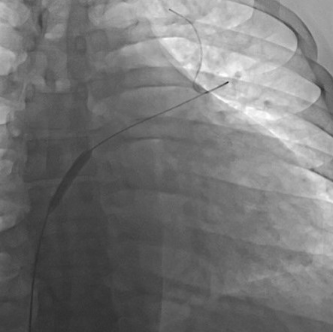

在征得患者同意之后,张主任先行选择性肺动脉造影,发现患者双肺动脉均存在弥漫性血栓(图2),测量肺小动脉楔压50/,显著高于正常,继而将导管通过卵圆孔未闭测量左心房压力为34/,同样显著高于正常。于是张主任毅然决定,先行卵圆孔未闭球囊扩张术(图3)减轻左心室前负荷,防止左心功能恶化,继而行肺栓塞球囊扩张术解除肺动脉梗阻。手术非常顺利,患者病情显著好转,术后当日晚上即可平卧,继而双下肢水肿消失,术后一个月患者日常活动毫无压力,心脏超声发现左心室射血分数自30%上升至46.6%。

(图3)对卵圆孔未闭实施球囊扩张术。